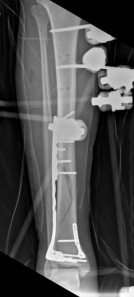

The patho-epidemiology of these injuries is inextricably linked to the incidence of acute compartment syndrome. High-energy axial loads result in rapid swelling, hemorrhage, and edema within the unyielding fascial compartments of the leg. As demonstrated in our reference case, clinical examination often reveals a tense, swollen limb necessitating an immediate four-compartment fasciotomy. The dual-incision technique remains the standard of care to decompress the anterior, lateral, superficial posterior, and deep posterior compartments. The presence of fasciotomy wounds further complicates the surgical approach for definitive internal fixation, requiring strict adherence to the principles of damage control orthopedics (DCO).

Image

Initial management in these high-velocity scenarios mandates the application of a spanning external fixator to achieve skeletal traction, restore length, and allow the soft tissue envelope to recover. This temporary stabilization minimizes ongoing secondary soft tissue trauma from mobile fracture fragments. However, the application of external fixators is not without risk; meticulous pin placement is required. For instance, calcaneal transfixion pins must be placed with strict attention to the neurovascular bundle to avoid iatrogenic tibial nerve irritation, an issue that required revision in the early phase of our index patient's care.